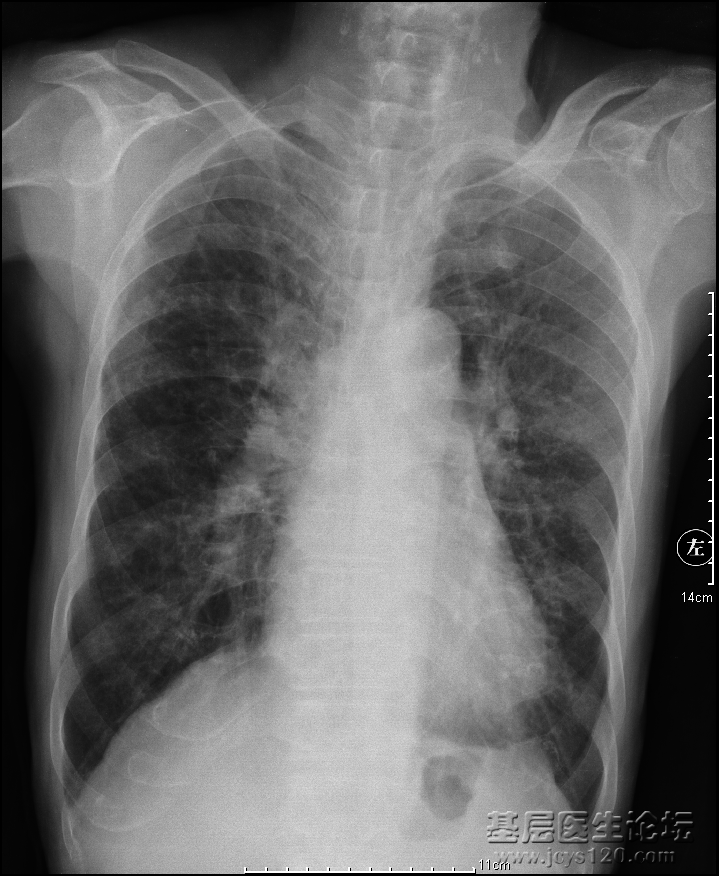

• 患者男,85岁,咳嗽咳痰,吸烟,余病史未知。 胸部正位 侧位 诊断报告:   两侧胸廓对称,气管上纵隔居中,右侧肺动脉干增粗,双肺纹理增粗紊乱以左肺较为明显,可见大量点片状低密度影呈蜂窝状。主动脉弓迂 ...  阅读全文>